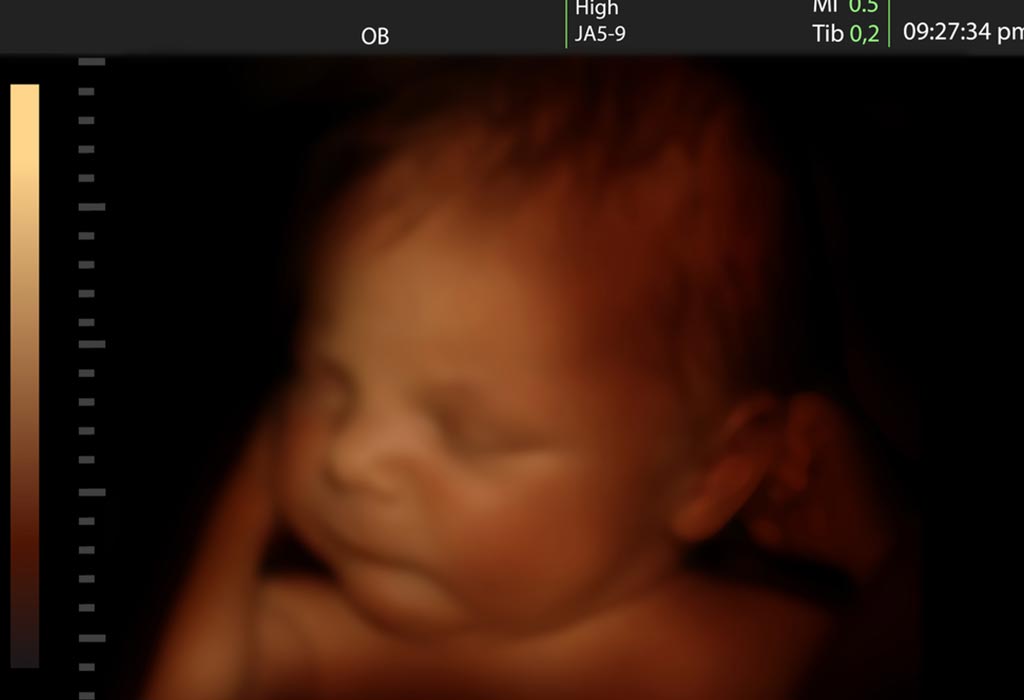

Thai nhi trong bụng mẹ có thể làm được nhiều hơn những gì bố mẹ nghĩ, bao gồm cả việc khóc. Bài viết dưới đây sẽ giúp bạn biết thêm nhiều điều thú vị về hiện tượng thai nhi khóc trong bụng mẹ:

- Thai Nhi Trong Bụng Mẹ Có Khóc Không?

- Biểu Hiện Quan Sát Được Khi Thai Nhi Khóc Trong Bụng Mẹ